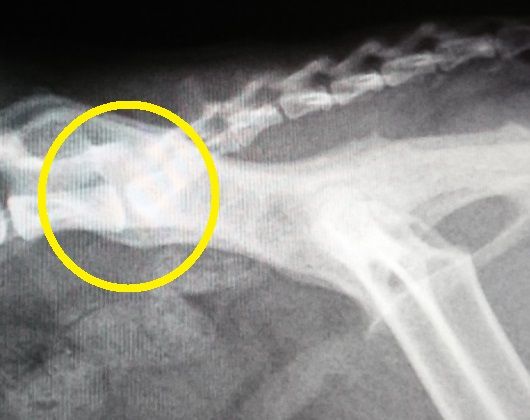

2012年:7歳のレントゲン

背骨と尻尾の付け根の骨の状態の経過を年を追って見てみると、若い頃は、骨と骨の隙間もしっかり開いてましたが、2015年のレントゲンでは、先ずは、隙間がかなり狭くなって来ており、更に、2016年のレントゲンでは、骨の下の部分に突起が、これを我が家ではトケトケと呼んでいます。